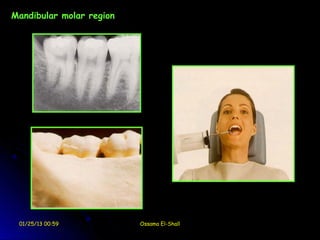

Mandibular molar region

01/25/13 00:59               Ossama El-Shall

Mandibular Molar

centered on second molar               film equidistant from lingual

surface of teeth; in this case the

film will usually contact lingual of

molars